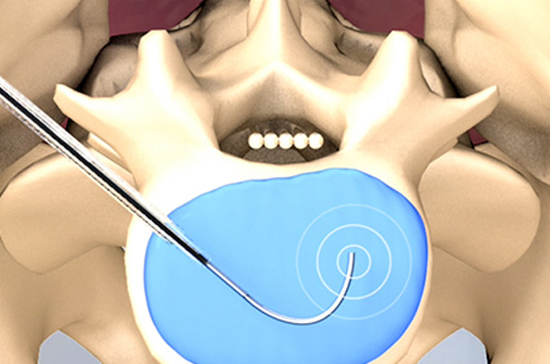

양방향 척추내시경 신경감압술

양방향 척추내시경 신경감압술은 약 4㎜ 가량 작은 구멍을 두군데 뚫어 내시경을 삽입해 협착된 부위를 제거하는 수술법입니다.

한쪽은 내시경을 삽입해 정확한 원인을 찾는 동시에, 다른 한쪽으로는 수술기구를 삽입해 척추관협착증의 주된 원인인 인대와 관절의 골극을 제거하는 첨단 수술 기법입니다.